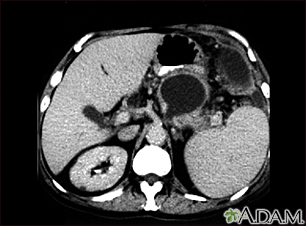

Pancreatic pseudocyst - CT scan